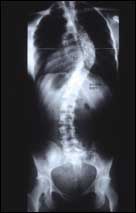

الجنف.. أسبابه.. أعراضه.. طرق العلاج

ثلاثة أسباب لانحناء الظهر والنساء أكثر عرضة من الرجال..!!

الجنف يعني انحناء العمود الفقري إلى الجانب (بعيداً عن المنتصف). ومن الأسماء البديلة للجنف انحناء العمود الفقري، والتحدب الجنفي .

هناك ثلاثة أسباب عامة للجنف هي السبب الولادي، والذي عادة ما يكون مرتبطاً بمشكلة في تشكل العمود الفقري أو انصهار الأضلاع أثناء نمو الجنين، والسبب العصب.........